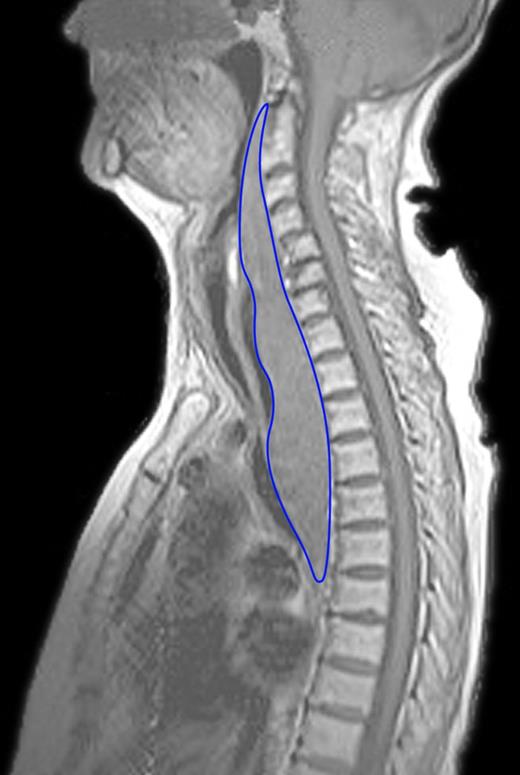

At the time of presentation, the patient experienced swallowing difficulties, globus sensation and malaise since 3 days with reduced oral intake. Progressive pain and mild dyspnea were present since 1 day. Physical examination revealed a subtle inspiratory stridor, the anterior lower neck was tender at palpation, but no evident ecchymosis or mass was found and signs of infection were absent. Laboratory data demonstrated an elevated prothrombin time—International Normalized Ratio of 9.49, an elevated PTH level (8.9 pmol/l, normal range 0.7–4.4 pmol/l) and a normalized calcium level (2.28 mmol/l, normal range 2.10–2.55 mmol/l) as a result of the calcimimetic drug therapy. An ultrasound study of the neck revealed a low-density mass dorsal of the right thyroid lobe possibly extending intrathoracically. Subsequent magnetic resonance imaging (MRI) showed an elongated retropharyngeal mass expanding from the second cervical vertebra into the posterior mediastinum with compression of the trachea and esophagus (Fig. 2).

MRI showing the elongated retropharyngeal mass anteriorly of the spine, compressing the trachea and esophagus. The mass starts at the level of the second cervical vertebra and expands into the posterior mediastinum until the level of the seventh thoracic vertebra. Length of the hematoma is 200 mm with an anterior–posterior diameter of 33 mm. Compression of the trachea to a minimal diameter of 3 mm.